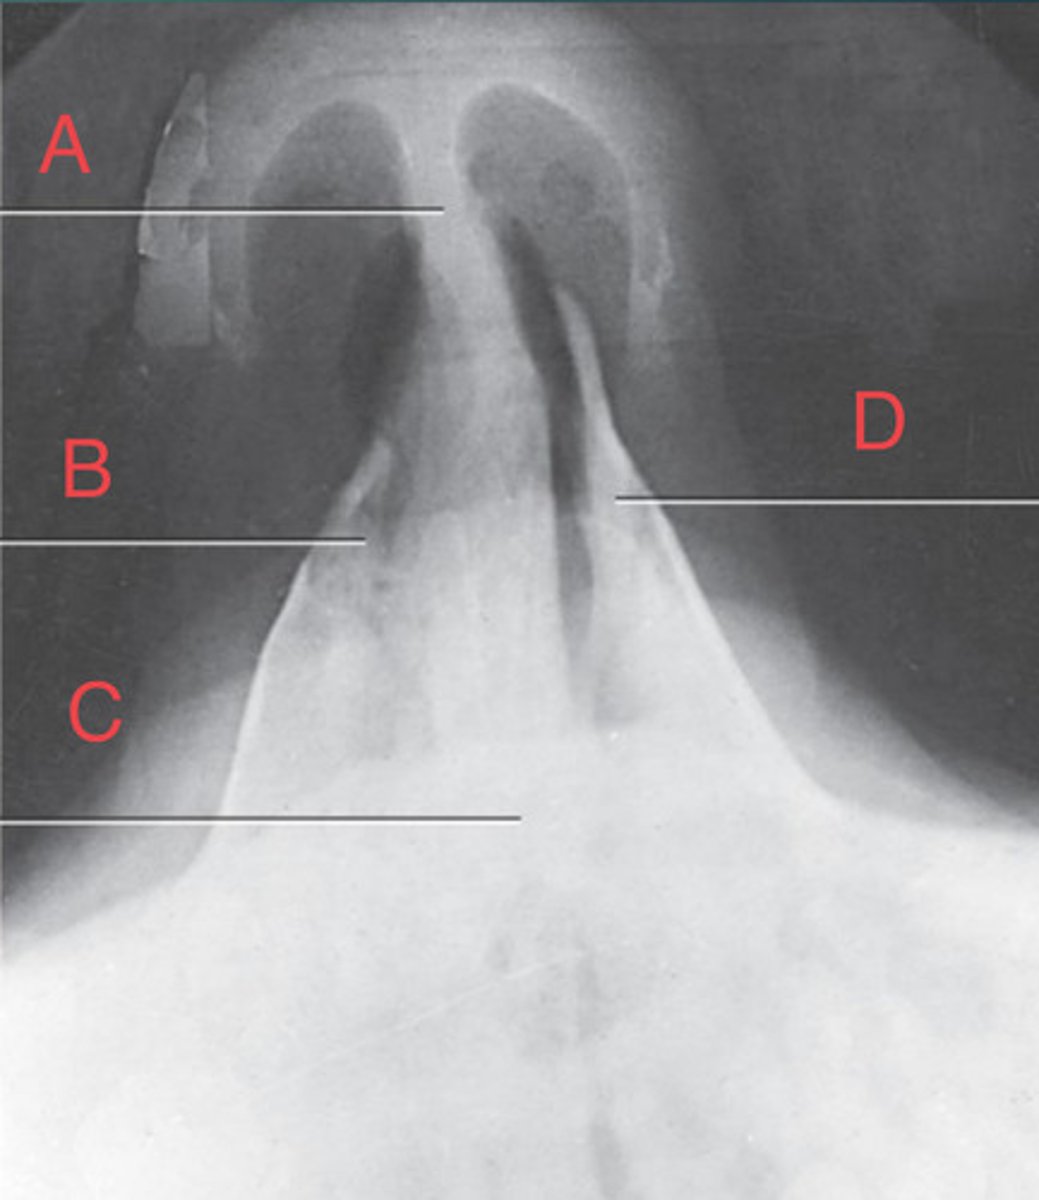

PA Caldwell Sinuses

What position?

frontal sinus of the frontal bone

A.

R. ethmoid sinus of the ethmoid bone

B.

crista galli of ethmoid bone

C.

L superior orbital fissure of the sphenoid

D.